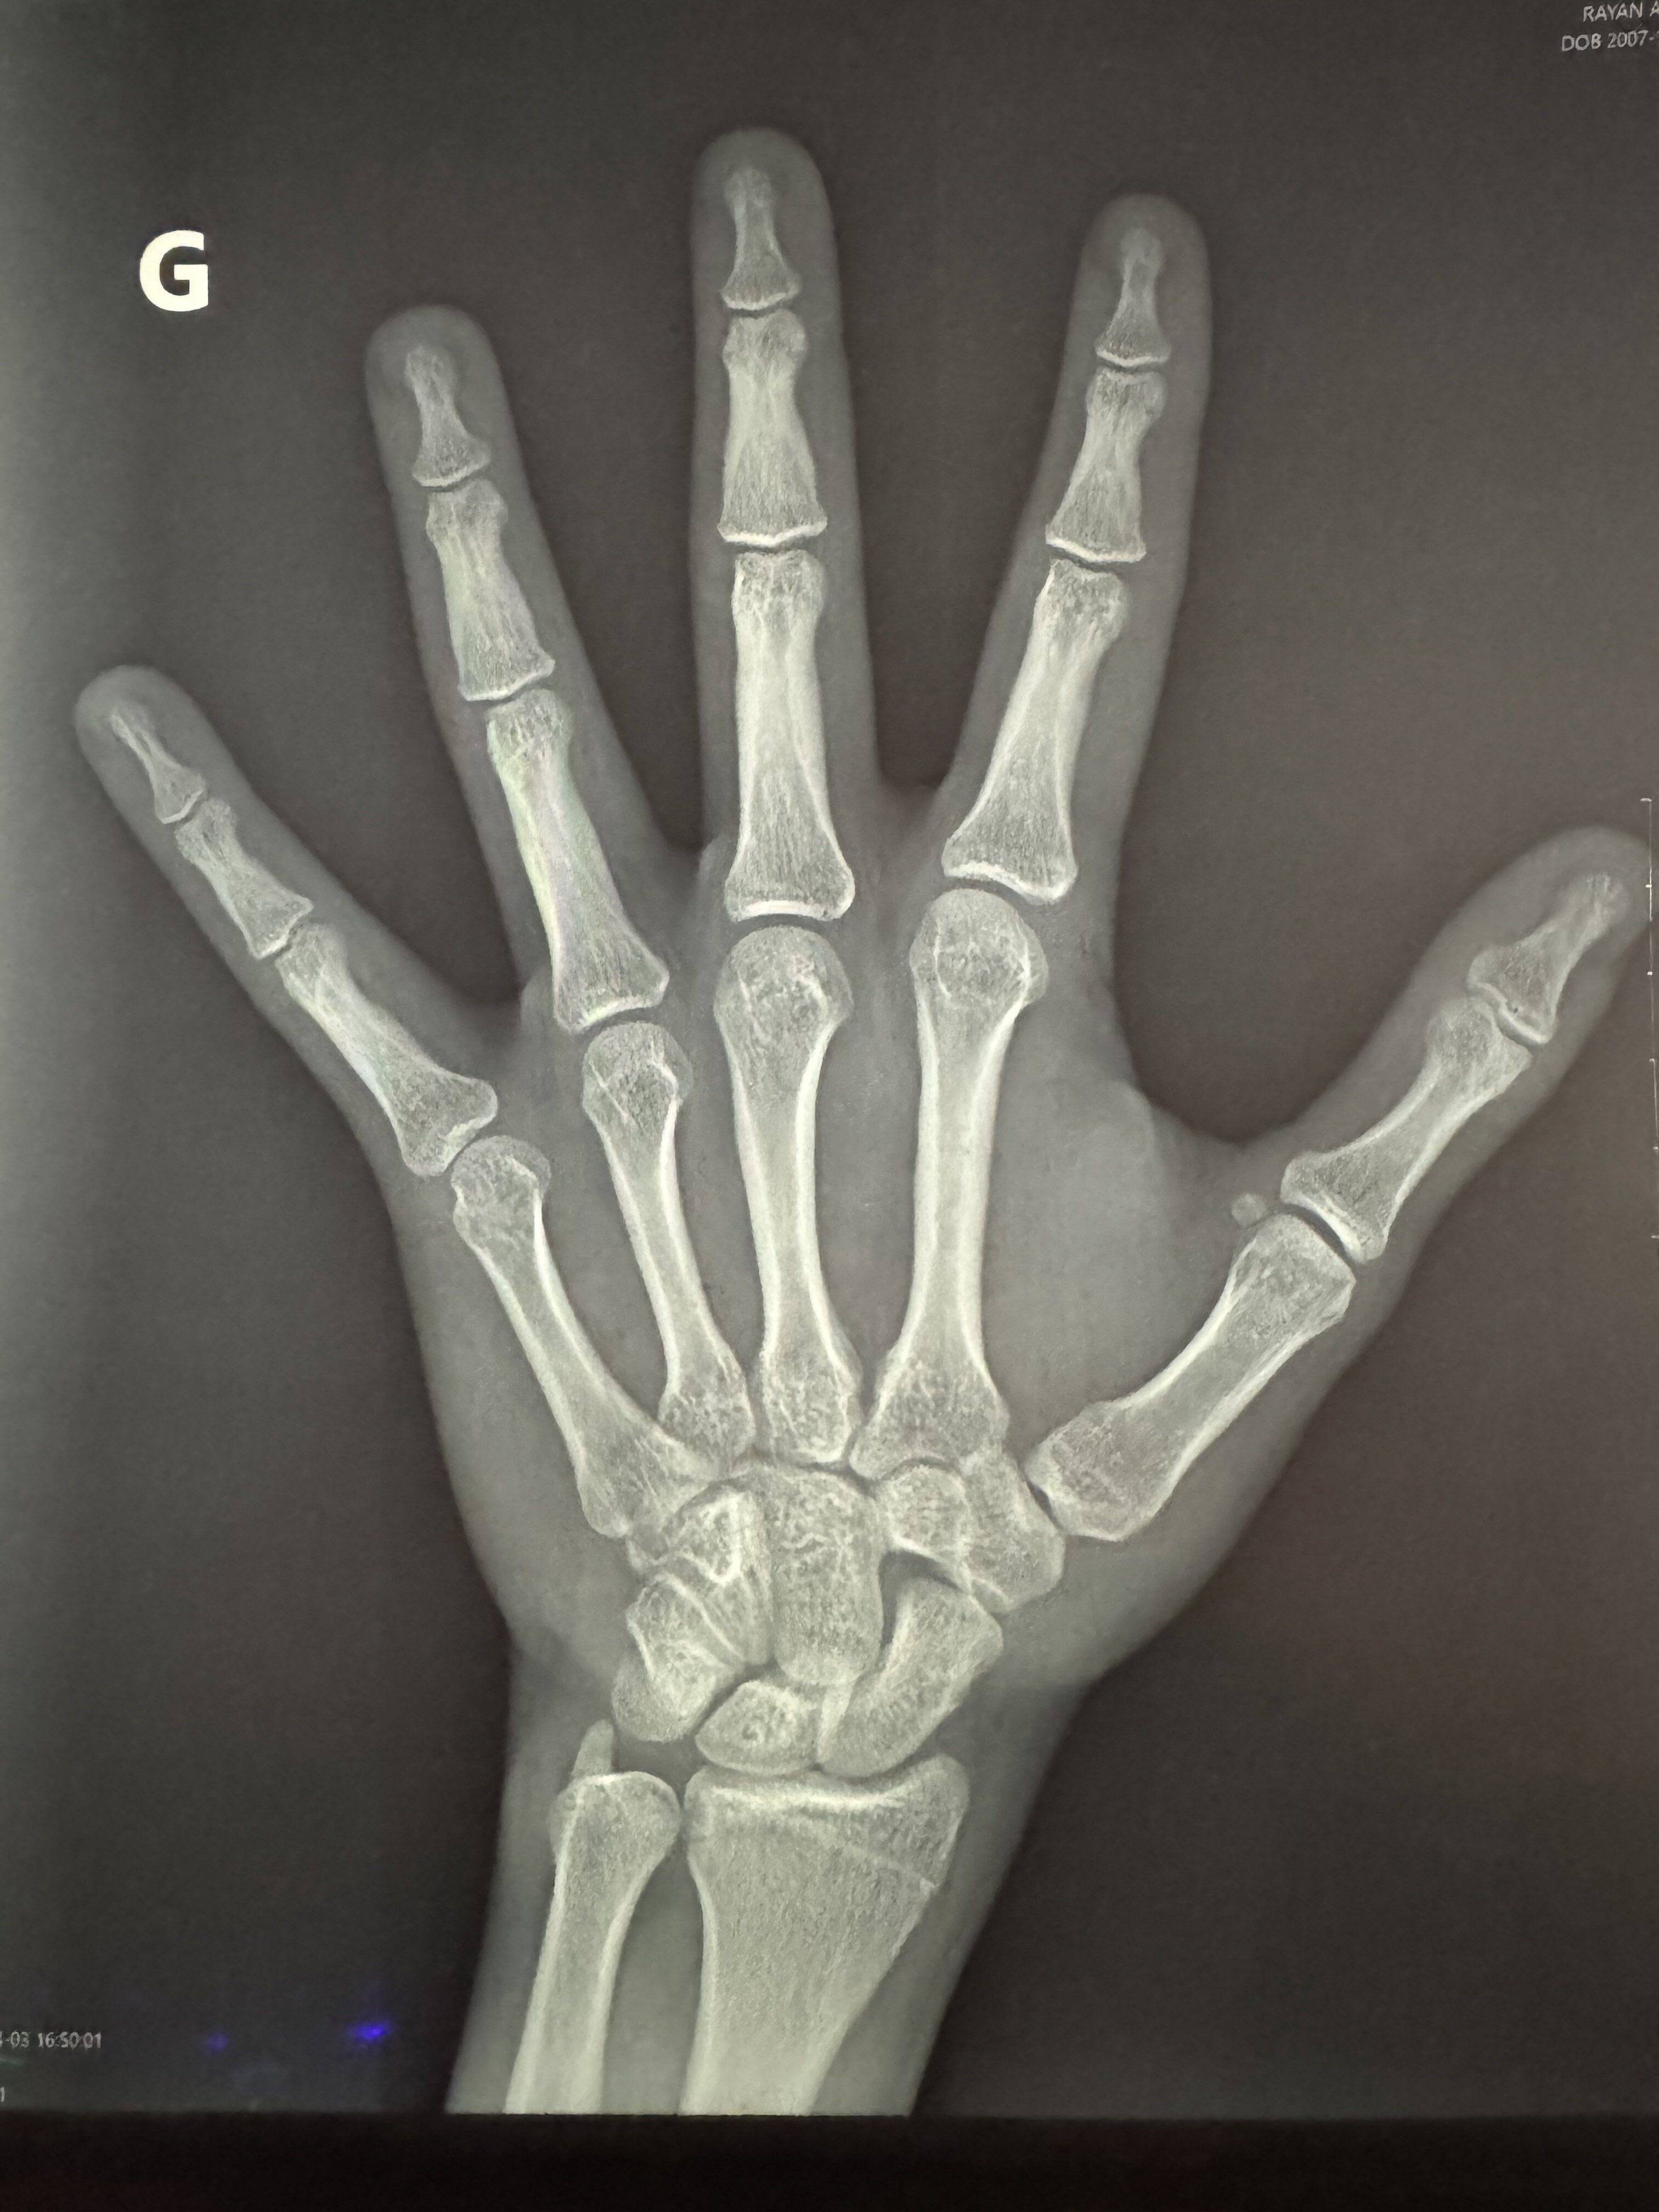

Do I can still grow or my grow plate is completely closed , I’m 18,5 years and my bones age is 17 7 months

its openDo I can still grow or my grow plate is completely closed , I’m 18,5 years and my bones age is 17 7 monthsView attachment 4879714

bro till 18 your bone structure is almost completed and rarely happen growth if somebody get a late puberty its depend when your puberty started and i think our hand bone devlopment is done till 17Do I can still grow or my grow plate is completely closed , I’m 18,5 years and my bones age is 17 7 monthsView attachment 4879714

Hey there's this crazy thing called Artificial Intelligence that has literally been used to spot cancers on X-rays.Do I can still grow or my grow plate is completely closed , I’m 18,5 years and my bones age is 17 7 monthsView attachment 4879714